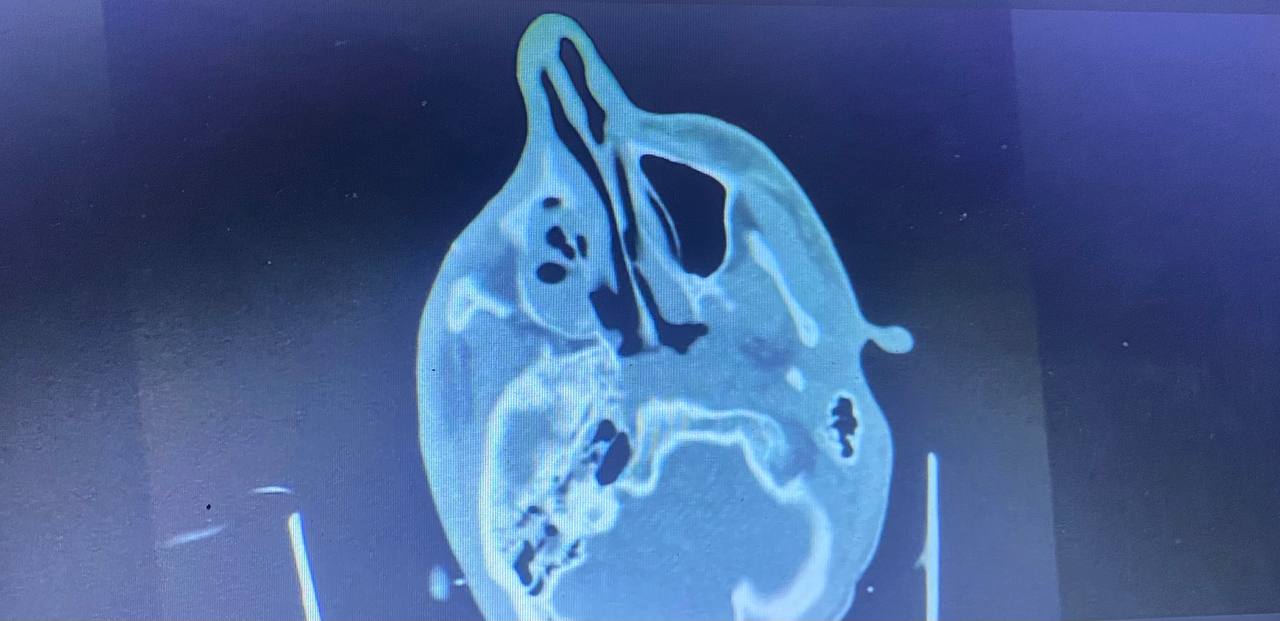

Разбил гайморовые пазухи. Врачи говорят, что в таких случаях человек истекает кровью. Выжить в такой ситуации просто невозможно.